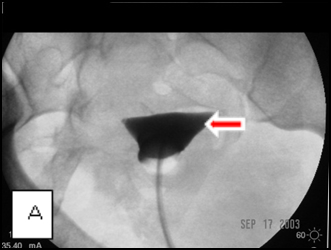

Images A, B, and C belong to a young woman who was referred to me for hysterosalpingography because of infertility and was shown at the examination to have bilateral cornual occlusion of the fallopian tubes. Image A shows contrast opacifying her endometrial cavity (red arrow), but not the fallopian tubes due to bilateral cornual occlusions. In image B, I have reopened the right cornual occlusion, filling a large right hydrosalpinx with radiocontrast (red arrow), and have a guide wire in the left fallopian tube (blue arrow), which implies relief of the obstruction. Image C, the final image, shows that both cornual occlusions are relieved, but there are bilateral large hydrosalpinges because of fimbrial adhesions, proven by the absence of contrast spill into the peritoneal cavity.